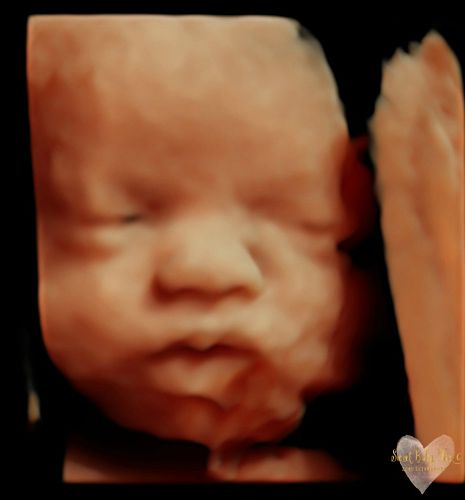

3D/4D/5D Ultrasound Gallery

Take a peek at our Photo Gallery. All of our 2D, 3D, 4D, HD elective ultrasound images are truly ours. They come directly off our machine from our highly trained staff. We can start getting great 3D/4D images as early as 10 weeks!